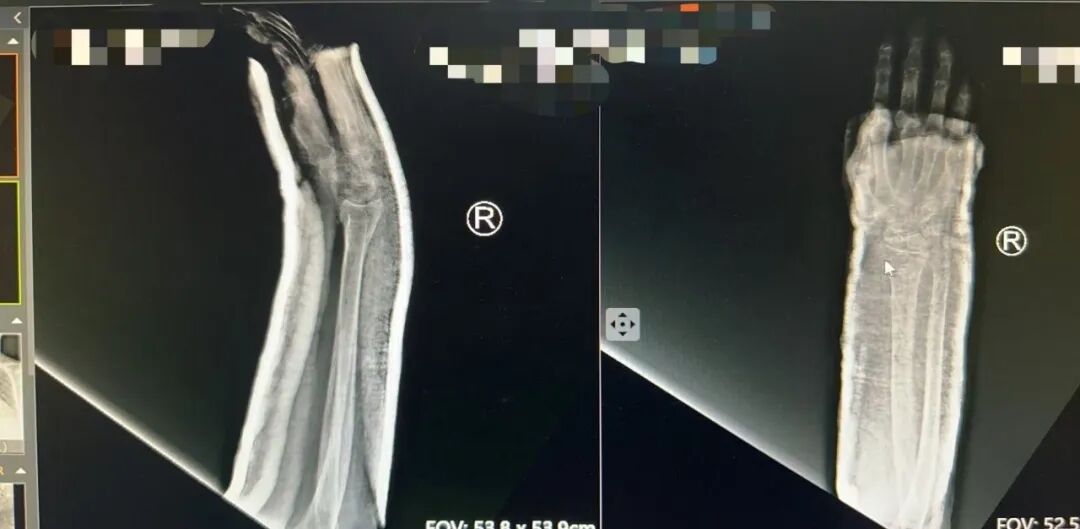

接诊的薛安邦主治医师第一时间为田奶奶仔细检查。老人的右腕部肿胀明显,呈现出典型的“餐叉样”畸形,一按就疼,腕关节活动完全受限。随后的X线片证实了诊断:右尺骨远端骨折伴桡骨远端骨折,骨折端移位明显。如果不及时处理,不仅会影响手腕功能,长期制动还可能引发压疮等一系列并发症,对90岁高龄的老人来说,风险极大。

复位后,团队立即为老人进行石膏外固定。复查X线片显示:骨折端对位对线良好,达到了解剖复位标准。田奶奶腕部畸形完全消失,疼痛明显缓解。